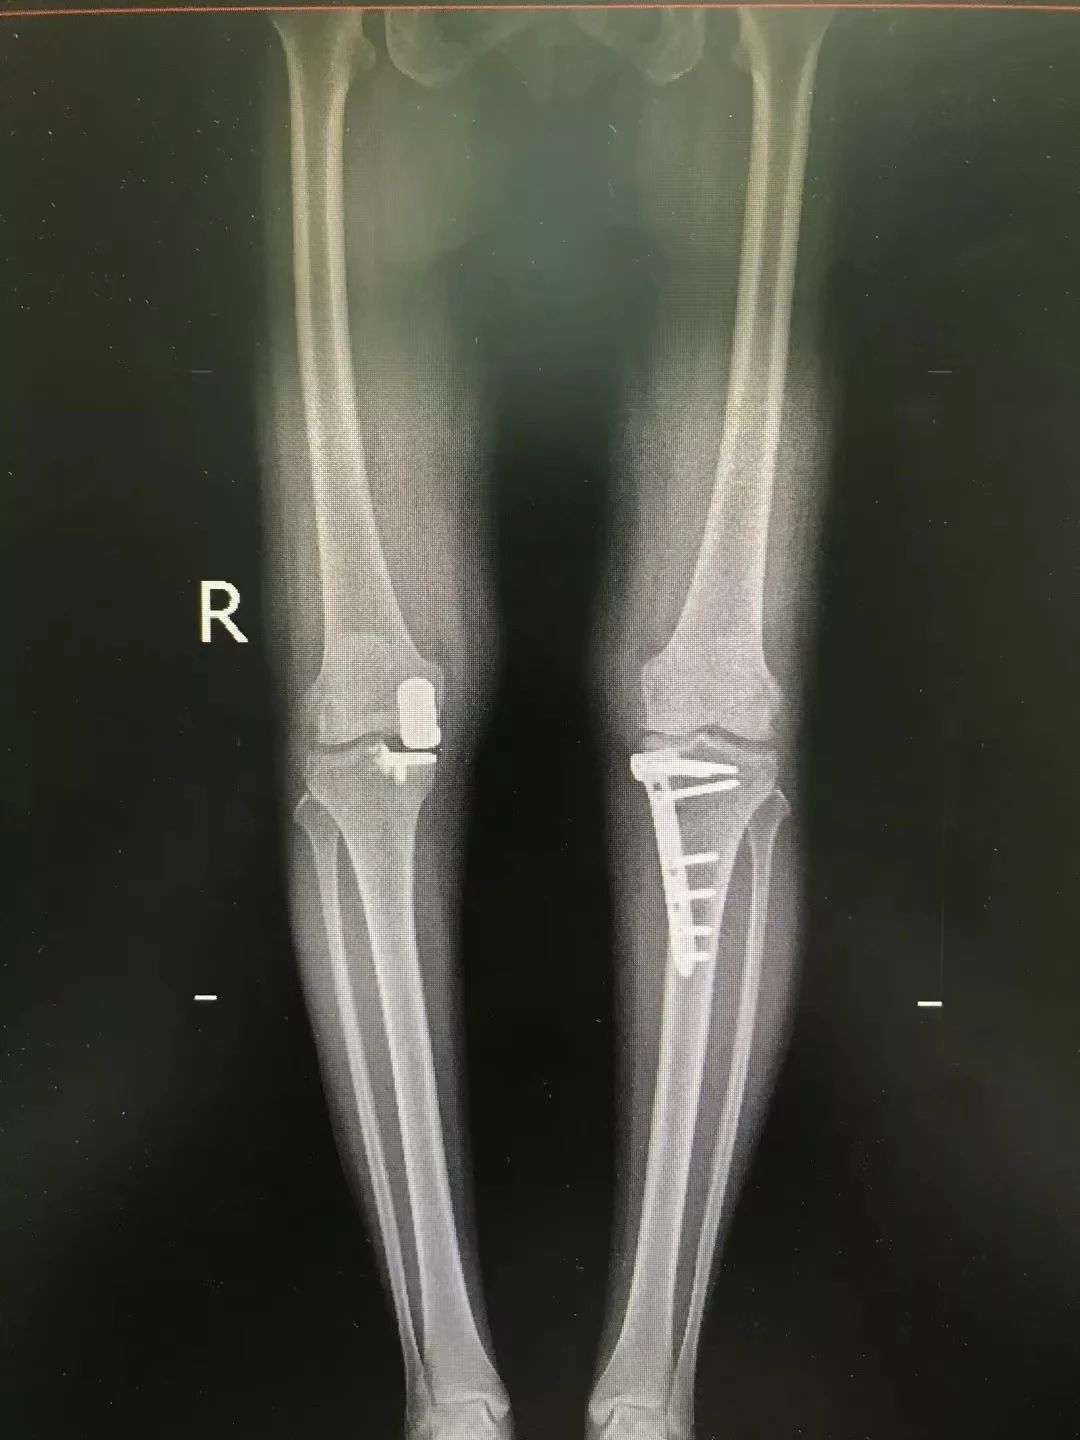

来自上海的李女士双膝疼痛10余年,左侧疼痛感更强烈,长期经口服消炎止痛药、理疗和关节腔注射玻璃酸钠等非手术治疗均收效甚微。在多处求医无门之后,李女士来到海南省人民医院运动医学科。经过王广积对其病情的仔细分析,诊断患者为双侧膝关节骨性关节炎,以内侧间室为重,左侧膝关节明显内翻畸形。

若按传统人工膝关节置换手术,可能会导致患者创伤大,且手术费用较高。考虑到患者较为年轻,后期或许还将面临二次或多次翻修手术。为了减少手术创伤及经济负担,王广积主任团队为患者开展了一期左侧胫骨高位截骨矫形术(HTO)和右侧单髁置换术(UKA)。“这是目前治疗膝关节骨性关节炎的有效的微创手术,在延缓膝关节炎的进展、改善关节功能的同时,还能最大程度减少手术创伤及费用。”王广积表示。